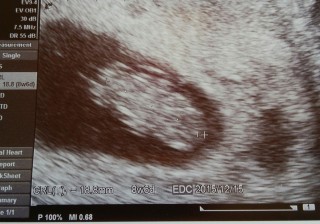

手や足ができてきて、赤ちゃんっぽい形になっててびっくり。 大きさは20.8mm。母子手帳を取りに行くよう言われました。

かわいい姿が見れて辛いツワリも一瞬ぶっ飛びました!!